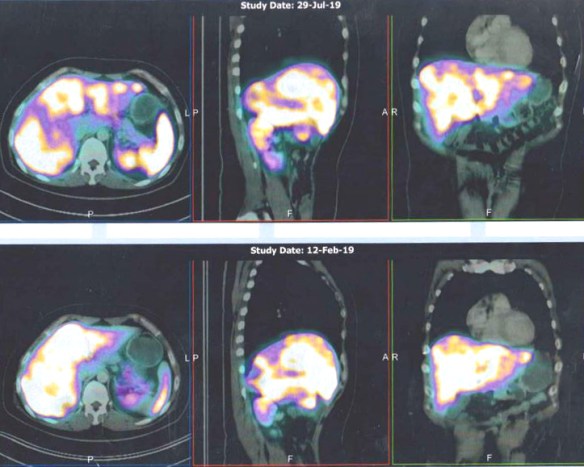

- PET scan on 14 September 2023 showed more serious condition.

- The metabolically active left lung mass with multiple neck, axillary and mediastinal nodes. Left pleura and bone lesions are likely due to primary lung malignancy.

- However, metastatic breast cancer recurrence cannot be excluded.